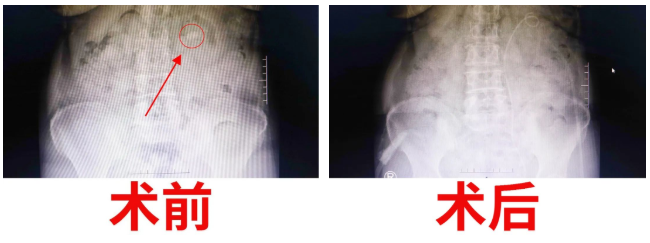

經(jīng)過(guò)泌尿外科醫(yī)護(hù)人員的密切觀察和精心護(hù)理,手術(shù)后的第三天,復(fù)查X光片,發(fā)現(xiàn)腎結(jié)石已消失得無(wú)影無(wú)蹤?!坝辛诉@樣先進(jìn)的機(jī)器,以及泌尿外科醫(yī)生團(tuán)隊(duì)高超的技術(shù),我們腎結(jié)石患者再也不用受病痛之苦了,這真是我們廣大腎結(jié)石患者的福音啊。”患者激動(dòng)的連聲道謝。一周后康復(fù)出院。